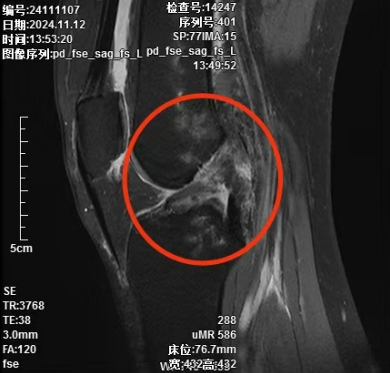

经接诊的况松主治医师细心查体并完善MRI检查后诊断为:

1. 左膝前交叉韧带断裂;

2. 左膝后交叉韧带断裂;

3. 左膝内外侧半月板Ⅲ度损伤;

4. 左膝关节内侧副韧带损伤;

5. 左股骨、胫骨骨挫伤;

6. 左股骨远端撕脱骨折。

▲术前核磁共振提示膝关节前、后交叉韧带断裂,内侧副韧带损伤